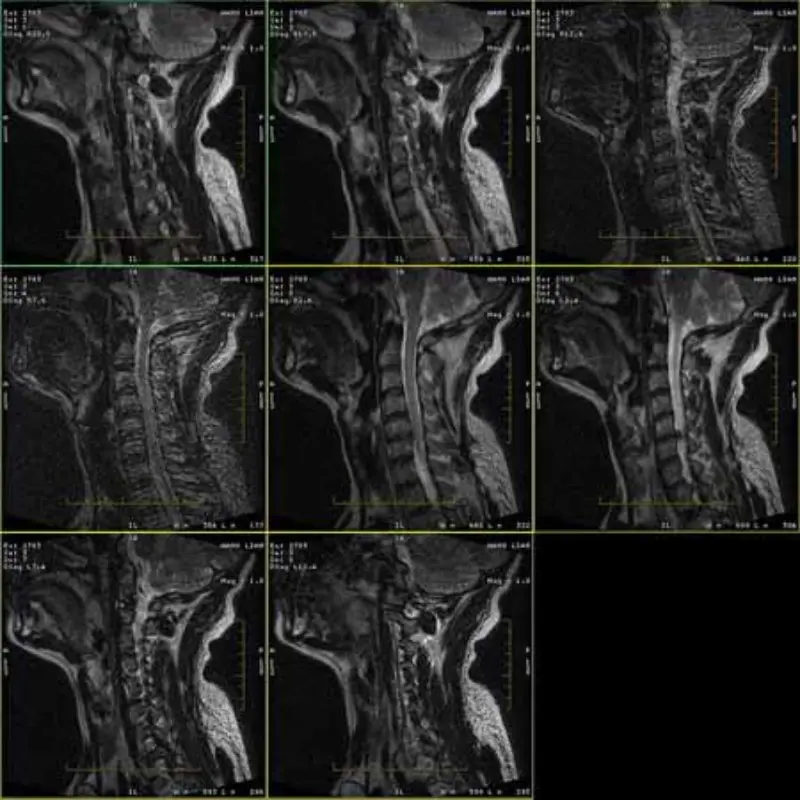

FRFSE ve GRE protokollerinin görüntüleri gölgelidir ve bazen düşük SNR görüntüleri tek bir seride görünür. Ancak SE protokolü görüntüleri normaldir.

Lütfen ekteki görsellere bakınız.